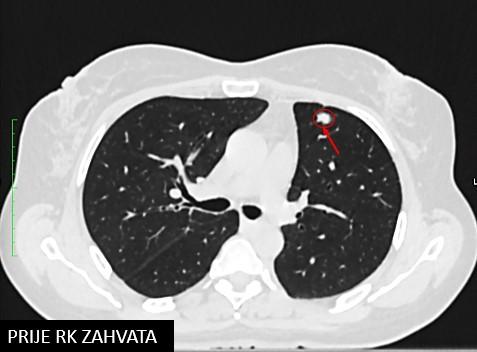

Bolesnica, rođena 1958. Dijagnoza: Adenocarcinoma lobi inferioris pulmonis sinistri